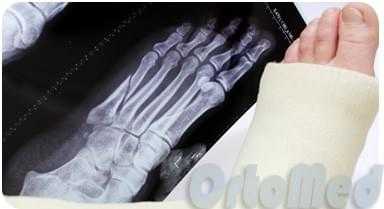

Переломы плюсневых костей

Переломы плюсневых костей по частоте занимают первое место среди всех переломов костей стопы. Обычно возникают при прямом воздействии травмирующей силы (сдавление стопы, падение тяжести или переезд стопы колесом). Могут быть множественными или одиночными. В зависимости от уровня повреждения выделяют переломы головки, шейки и тела плюсневых костей.

Одиночные переломы плюсневых костей очень редко сопровождаются значительным смещение фрагментов, поскольку оставшиеся целыми кости плюсны выполняют функцию естественной шины, удерживая отломки от смещения.

При одиночных переломах плюсневых костей выявляется локальный отек на тыле и подошве, боль при опоре и прощупывании. Множественные переломы плюсневых костей сопровождаются выраженным отеком всей стопы, кровоизлияниями, болью при пальпации. Опора затруднена или невозможна из-за боли. Возможна деформация стопы. Диагноз подтверждается данными рентгенографии в 2-х проекциях, а при переломах основания костей плюсны – в 3-х проекциях.

При переломах костей плюсны без смещения накладывают заднюю гипсовую шину сроком на 3-4 недели. При переломах со смещением проводят закрытое вправление, выполняют открытый остеосинтез или накладывают скелетное вытяжение. Срок фиксации при таких переломах костей стопы удлиняется до 6 недель. Затем пациенту накладывают специальную гипсовую повязку «с каблучком», а в последующем рекомендуют использовать ортопедические вкладки.